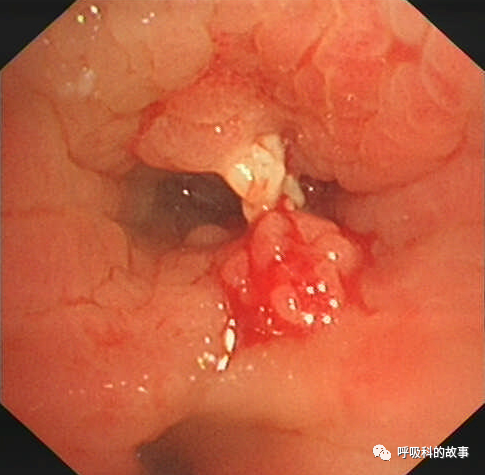

可是又經過了三週,黃女士症狀依舊沒有改善,這一次她終於聽話地住進了病房,我們給她做了氣管鏡檢查,結果發現右下葉支氣管開口有肉芽組織堵塞了管腔,將這些肉芽組織清理後,終於暴露出了一個骨性異物,最終我們將其鉗出。

對於慢性咳嗽不愈,CT顯示在同一部位反覆感染,氣管內有高密度影者,一定要警惕支氣管異物的可能,及時進行氣管鏡檢查。而患者也希望能充分配合醫生,才能及時解決病痛。